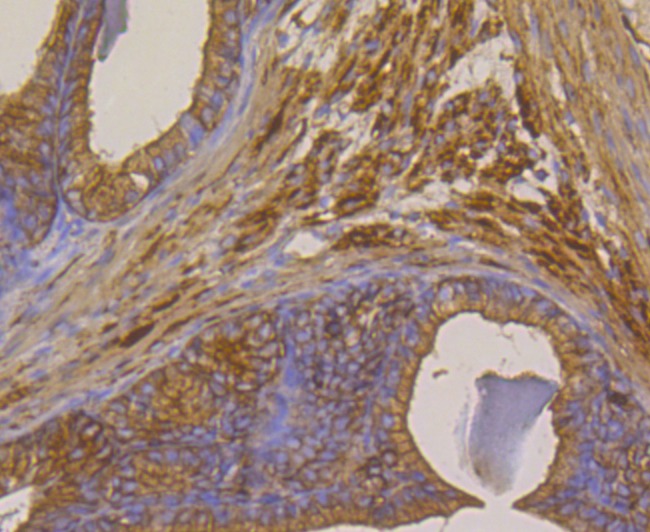

Anti-METAP2 Antibody (2D279) is a Rabbit antibody targeting METAP2. Anti-METAP2 Antibody (2D279) can be used in FCM,ICC,IF,IHC,WB.

| Verified Activity | 1. Western blot analysis of Methionine Aminopeptidase 2 on Hela cell using anti-Methionine Aminopeptidase 2 antibody at 1/1,000 dilution. Positive control: Lane 1: Daudi, Lane 2: K562, Lane 3: Mouse thymus, Lane 4: Mouse kidney. 2. Immunohistochemical analysis of paraffin-embedded rat seminal vesicle tissue using anti-Methionine Aminopeptidase 2 antibody. Counter stained with hematoxylin. 3. Immunohistochemical analysis of paraffin-embedded human tonsil tissue using anti-Methionine Aminopeptidase 2 antibody. Counter stained with hematoxylin. 4. Immunohistochemical analysis of paraffin-embedded human prostate cancer tissue using anti-Methionine Aminopeptidase 2 antibody. Counter stained with hematoxylin. 5. Immunohistochemical analysis of paraffin-embedded human kidney tissue using anti-Methionine Aminopeptidase 2 antibody. Counter stained with hematoxylin. 6. Immunohistochemical analysis of paraffin-embedded mouse testis tissue using anti-Methionine Aminopeptidase 2 antibody. Counter stained with hematoxylin. 7. ICC staining Methionine Aminopeptidase 2 in LOVO cells (green). The nuclear counter stain is DAPI (blue). Cells were fixed in paraformaldehyde, permeabilised with 0.25% Triton X100/PBS. 8. ICC staining Methionine Aminopeptidase 2 in PC-3M cells (green). The nuclear counter stain is DAPI (blue). Cells were fixed in paraformaldehyde, permeabilised with 0.25% Triton X100/PBS. 9. ICC staining Methionine Aminopeptidase 2 in SH-SY-5Y cells (green). The nuclear counter stain is DAPI (blue). Cells were fixed in paraformaldehyde, permeabilised with 0.25% Triton X100/PBS. 10. Flow cytometric analysis of Daudi cells with Methionine Aminopeptidase 2 antibody at 1/100 dilution (purple) compared with an unlabelled control (cells without incubation with primary antibody; yellow). Alexa Fluor 488-conjugated goat anti-rabbit IgG was used as the secondary antibody. ![]() ![]() ![]() ![]() ![]() ![]() ![]() ![]() ![]() ![]() |